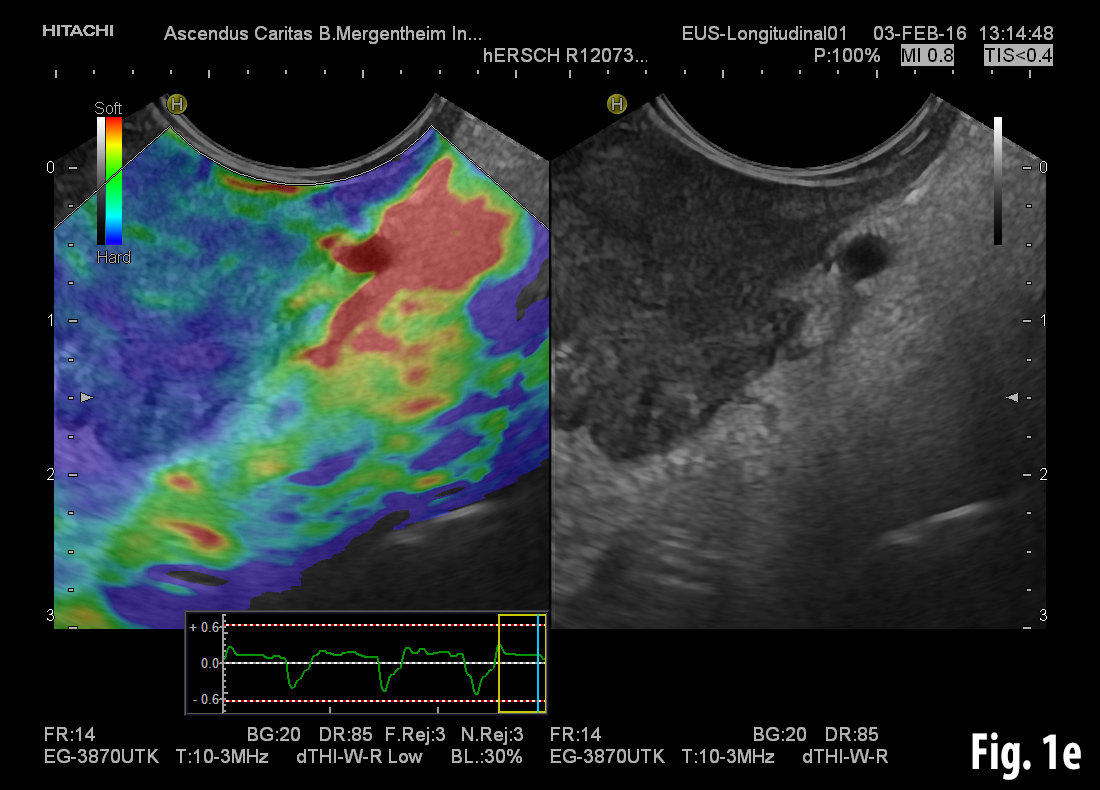

Conventional B-mode ultrasound revealed a mass lesion in the gallbladder region (a) and air bubbles within the liver (aerobilia) (b). Contrast enhanced ultrasound showed arterial enhancement as a sign of neoplasia (c). Endoscopy revealed a gallstone in the duodenal bulb (d). Elastography showed stiff tissue (blue) supportive of neoplasia (e). Details of elastography are explained in the EFSUMB guidelines on elastography [(1, 2)].

![Bouveret syndrome</br> [Apr 2016]](http://s834315022.websitehome.co.uk/wp-content/uploads/2020/11/cotm_april2016-fig1e.jpg)